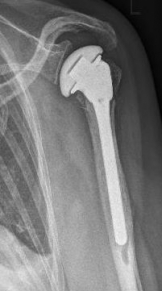

Picture: In the above pictures, a slightly shifted subcapital humeral fracture was internally splinted using intramedullary nail. The left picture is a follow-up examination half a year after the accident and shows the complete healing of the fracture with correct position of the bone.

Picture: A subcapital upper arm fracture was treated with a prosthesis. The humeral head was completely removed and replaced by the prosthesis. This is anchored in the upper arm with the prosthesis shaft.